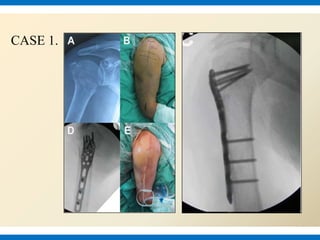

CASE 1.

Proximally a 5-6cm longitudnal incision from the tip of acromion down the lateral aspect

of upper arm. The length and position of distal incision depends on the site of fracture and